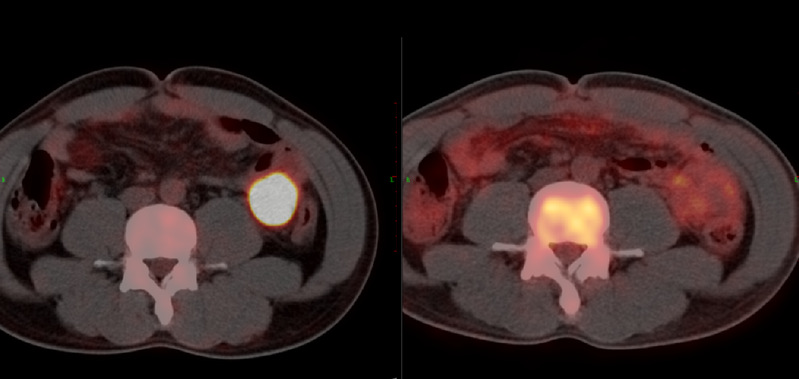

在完成各项临床研究报批后,2020年5月26日,浙大团队为孙先生输注PD1-19bbz CAR-T细胞,回输后的6月9日,孙先生CAR-T细胞回输后14天各项指标正常,经评估后出院,在回输后1个月进行PET-CT评估,结果显示原腹腔侵犯肠道粘膜部位的大包块肿瘤已完全消失。如今孙先生无病生存已超过2年。